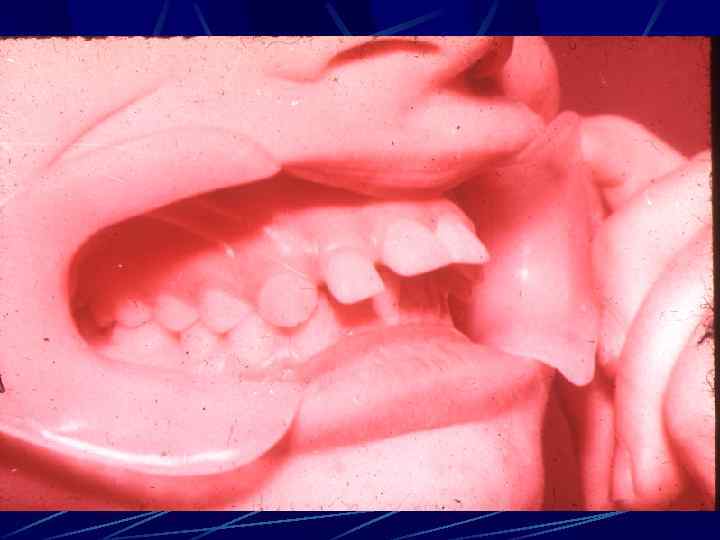

АНОМАЛИИ СТРОЕНИЯ И ПОРОКИ РАЗВИТИЯ ЗУБОВ Сверхкомплектный зуб сместил вестибулярно-комплектный резец и прорезался нёбно